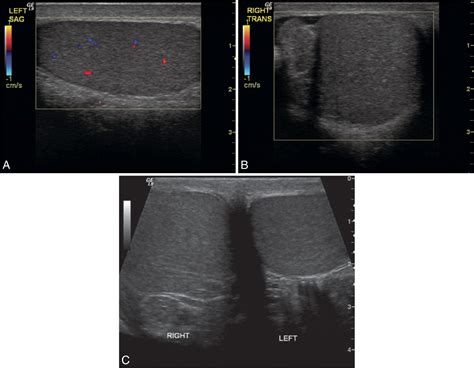

• Ultrasound: This is the most common diagnostic tool for testicular pain. A scrotal ultrasound uses sound waves to create images of the testicle, allowing the doctor to see blood flow, identify fluid buildup, or detect tumors.

These tests are essential because they provide objective data that a physical examination alone cannot yield. For example, an ultrasound can definitively distinguish between the reduced blood flow seen in torsion and the increased blood flow typically associated with inflammation.